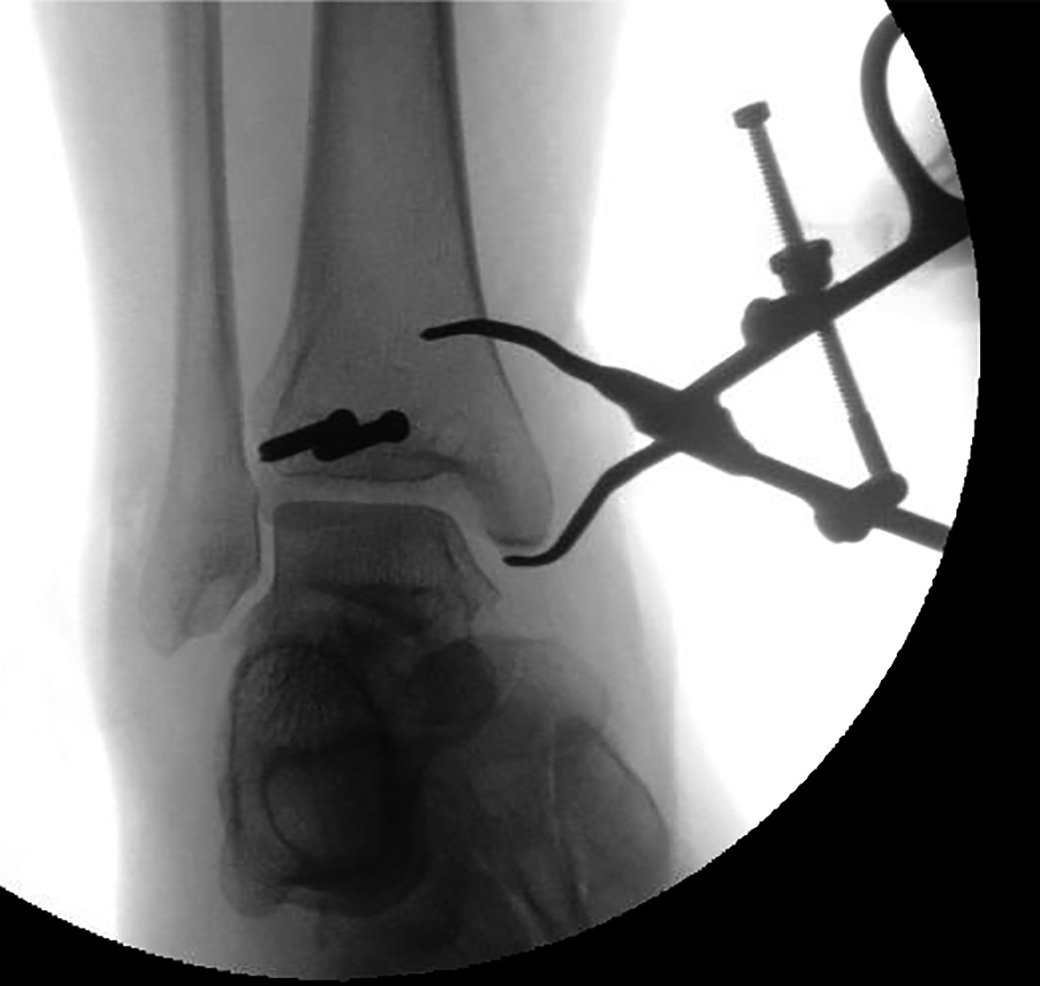

Versatile set of fracture reduction clamps, each with a specific tine design that allows for appropriate vector placement so that anatomic reduction can be obtained in a number of different types of fractures

• 1.9 mm tines allow for a snug fit in 2 mm drill holes

• Tines angled to prevent clamp “slippage” with compression

• Straight tines can be placed deep within bone which allows for far cortex compression.

• Example applications: any transverse fracture (straight-straight clamp), both bone forearm fractures, olecranon fractures, medial malleolus fractures, and many more.